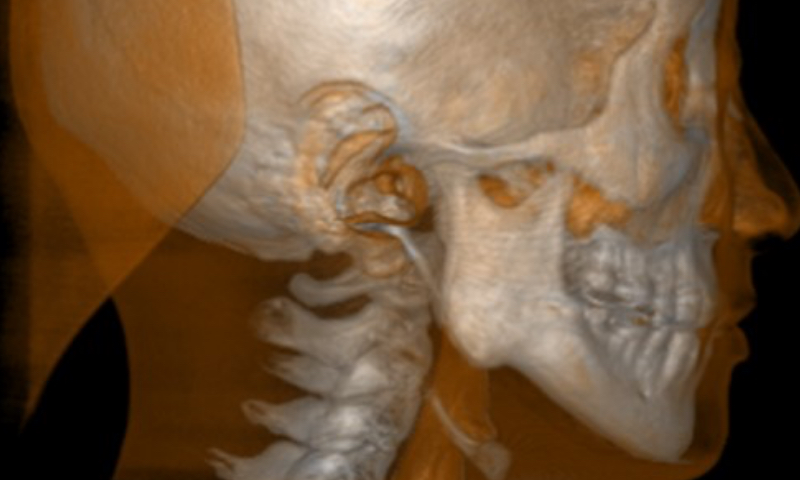

エックス線の水平入射

エックス線を水平に入射することで、エックス線の散乱を最小限にします。

金属アーチファクトを最小化し、関心部位への陰影障害を極小にします。![]()

画質の向上はもちろん、よりエックス線を抑えた撮影が実現。